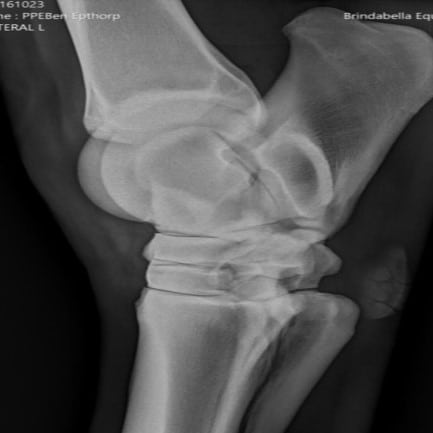

Lola Epthorp

AN EVALUATION OF THE EFFECTIVENESS OF EQUINE ALLOGENEIC CHONDROGENIC-INDUCED MESENCHYMAL STEM CELLS IN TREATING OSTEOARTHRITIS